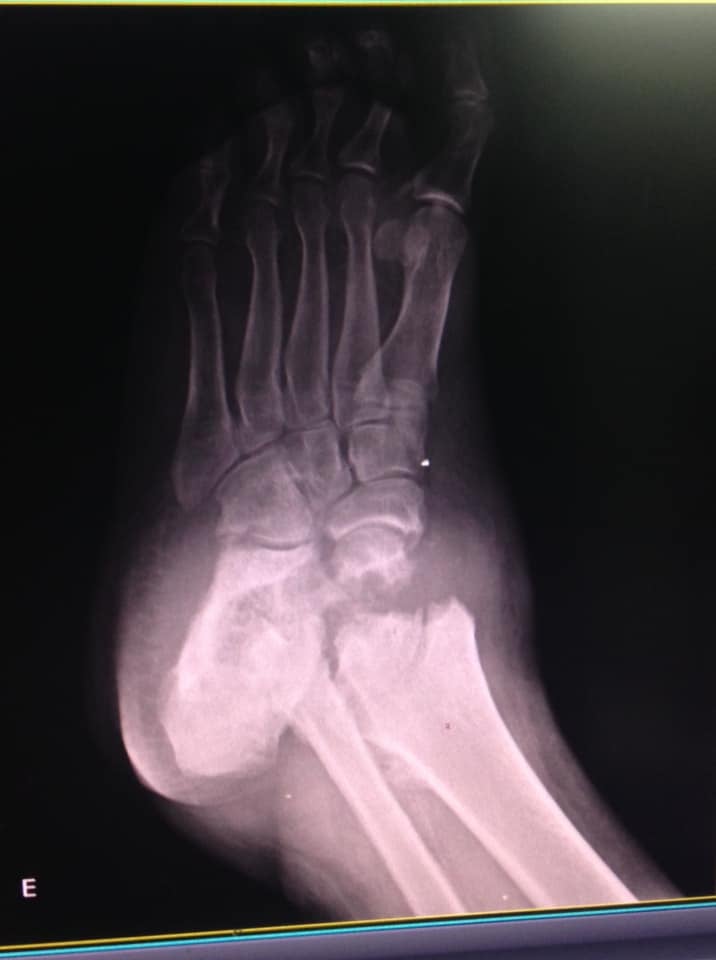

‘’Eu com 35 anos de idade tenho que aceitar ficar sem andar porque o país em que vivo não cobre a cirurgia? Aceito que não vou mais andar?’’, questionou a paciente. Ela apresentou várias radiografias e diz que os pés ‘’desabaram’’ por conta da doença rara.

‘’…não precisa ser médico, tão pouco especialista para ver as fraturas, elas são enormes e gravíssimas e se vê a olho nu’’, lamentou mais uma vez.